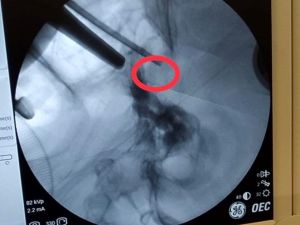

Hastanın beyindeki tümörü burun deliğinden çıkardılar